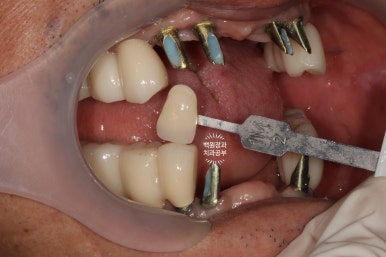

임시보철물을 제거하고 내부의 기둥이 보이는 모습입니다.

환자분과 함께 원하시는 치아 색상을 정해서 기공소에 전달하면, 이제 드디어 최종 보철물이 제작되어 옵니다.

보시면 치아와 기둥이 모두 연결되있는 것을 확인하실 수 있죠? 그리고 잘~보시면 임시치아의 외형도 보입니다.

(다시봐도 임플란트 좀 잘 했네요. 역시 나야!?)